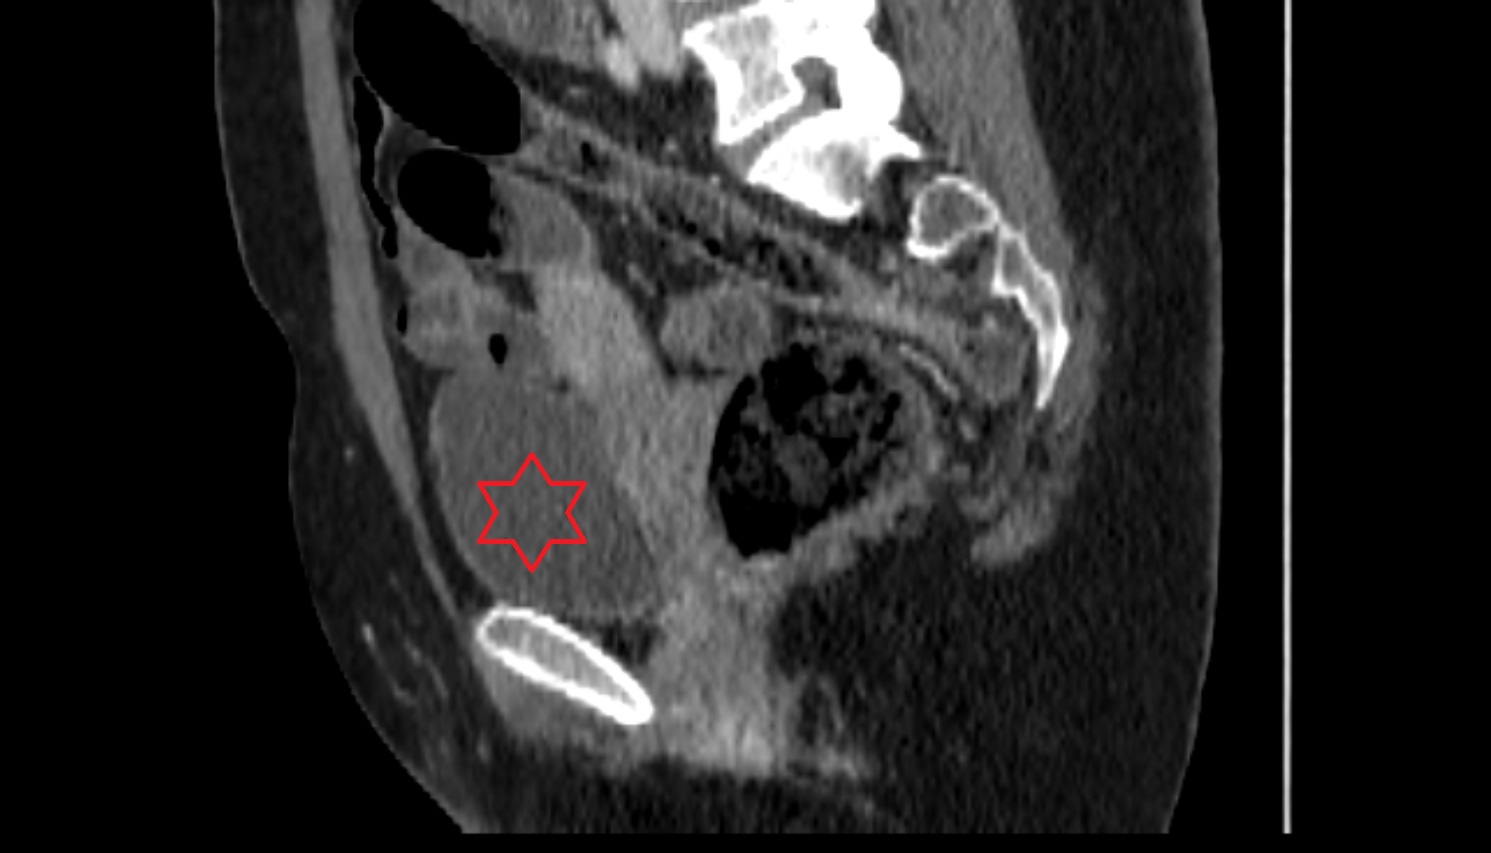

- Uterus

- kidneys

- Right kidney

- Left kidney

- Ureters

- Left ureter

- Right ureter